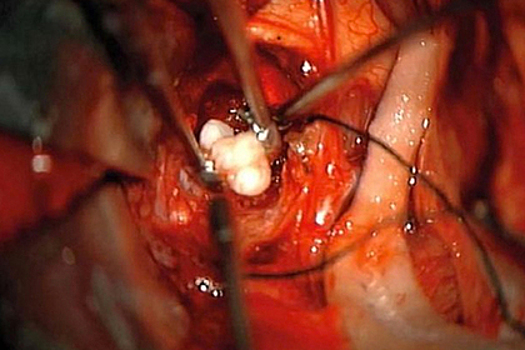

В Мэриленде, США, во время операции врачи обнаружили в мозге у младенца несколько полноценных зубов. Об этом сообщает британское издание Daily Star. Четырехмесячному ребенку диагностировали редкую врожденную доброкачественную опухоль головного мозга под названием краниофарингиома. Чтобы удалить новообразование, врачи решили сделать операцию. Во время нее они обнаружили у мальчика в мозге сформированные зубы. По словам медиков, это первый подобный случай за всю историю. Они не исключают, что патологию могла спровоцировать опухоль. Ученые давно склоняются к тому, что она образуется из тех же клеток, что и зубы. Однако по словам нейрохирурга медицинского центра университета Мэриленда Нарлина Бити (Narlin Beaty), при краниофарингиоме такое было бы невозможно. Особенно учитывая то, что в столь юном возрасте у мальчика просто не могли сформироваться зубы. Сейчас младенец находится в стабильном состоянии, его здоровью ничего не угрожает. Зубы, извлеченные из его мозга, переданы патологу для дальнейшего изучения. Ранее сообщалось, что врачи выходили ребенка с аномально большой опухолью. Одной из возможных причин ее появления они называют недоразвитого сиамского близнеца-паразита.